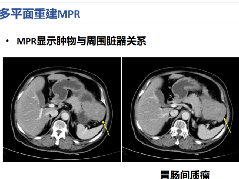

冠状面:冠状面稳态自由进动序列/单次激发T2WI序列。

在横轴位和矢状位定位,扫描范围包括肝脏前后缘,合理调整扫描范围,需包括整个病变范围。

上腹部的扫描应首先扫描范围较大的冠状面图像,以便对病变及周围组织器官作出大体地评估,更有利于精准地定位和扫描方案的制定。

冠状位:冠状位平衡期/延迟期增强补充序列

在横轴位及矢状位上定位,范围包括整个肝脏及病变范围。

大范围的冠状位增强序列有助于对血管、胆管、十二指肠区域以及周围受累情况的评估,